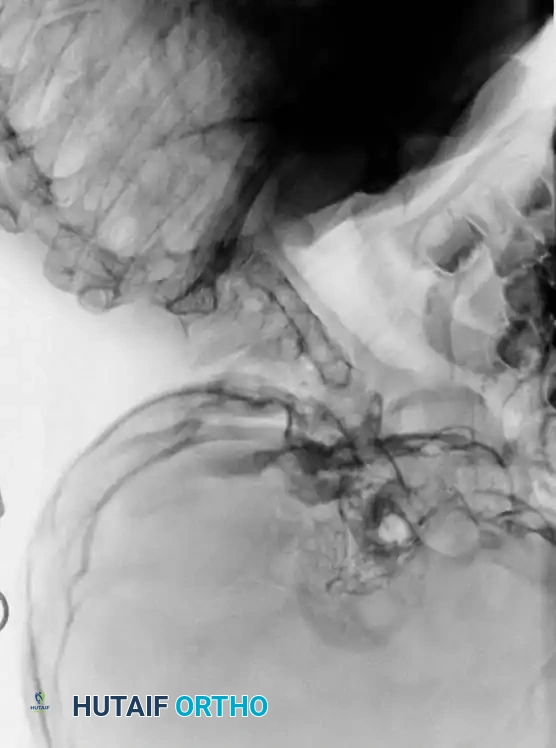

Dynamic Imaging

Lateral flexion-extension views are the most critical plain films obtained. They are essential for identifying occult atlantoaxial instability or hypermobility at an open segment adjacent to a fusion block.

Surgical Warning: Patients with Pattern 3 fusions are at extreme risk for adjacent segment disease. On dynamic lateral radiographs, the cervical spine will appear to "hinge" or subluxate at this single open segment. Prophylactic stabilization may be indicated if progressive neurological deficits or dynamic instability is documented.